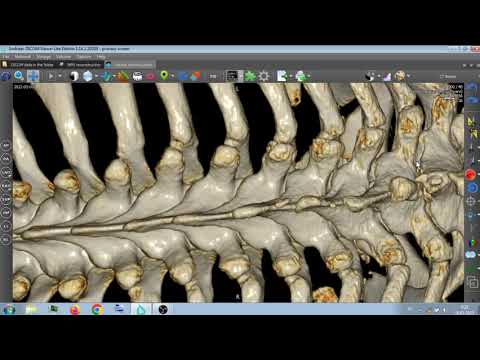

КТ ПОЗВОНОЧНИКА . ПЕРЕЛОМ ЗУБЧАТОГО ОТРОСТКА C7

Рассмотрите возможность использования МРТ или КТ для получения более детальной информации о состоянии позвонка.

Сравните рентгеновские снимки с нормальными изображениями для лучшего понимания патологии.